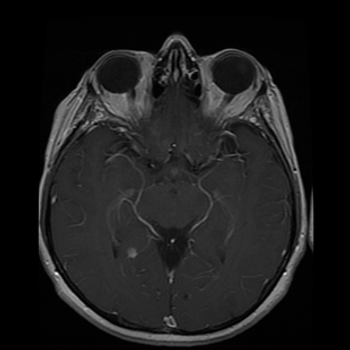

35-year-old female with prior history of breast carcinoma presented with frontal headaches.